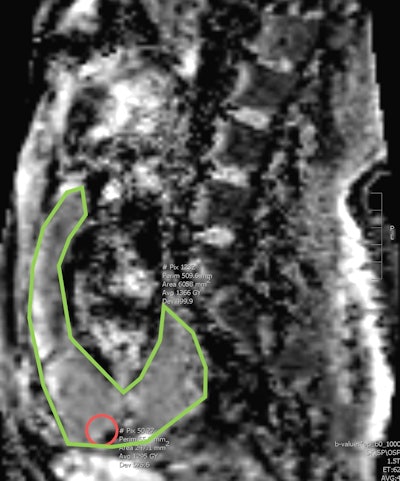

ADC MRI of a sagittal section shows areas of whole placenta segmentation (marked in green) and a small area of regional segmentation (red circle). Figures courtesy of Hiba Alessa and Dr. Elspeth Whitby.

ADC values were obtained from the area above the bladder and the entire placenta on a midline sagittal image by two readers. Heterogeneity of the placenta and placental dark bands were also noted. A pathological diagnosis was obtained from the medical records. Texture study of a sample size of 33 images was also analyzed using a radiomics program (LIFEx) by a single reader.